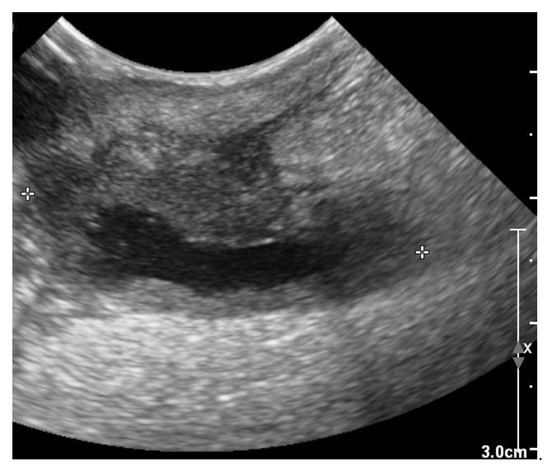

The recheck examination 2 weeks later revealed no abnormalities with inspection and palpation of the region where previously the wound was located over the right jugular vein. Ultrasonography showed no subcutaneous fluid accumulation around the pacing lead, but there was a small region of hypoechoic tissue visible (Figure 9).

Figure 9. Two-dimensional grayscale ultrasonographic image at the site of the previous swelling at the level of the jugular venous access shows a hypoechoic tissue of about 2.5 mm adjacent to the pacing lead, which is displayed in cross section.

Clindamycin administration was continued until the next recheck examination, again 2 weeks later. At this time the dog was still doing clinically good and ultrasonographic changes around the cervical part of the pacing lead showed no fluid accumulation; however, the hypoechoic tissue was still present. Under ultrasound guidance a fine-needle aspiration biopsy was taken from this hypoechoic tissue. Again, specific caution was exercised to avoid puncturing the pacing lead. Cytologic examination revealed no inflammatory cells. Based on this finding, clindamycin therapy was stopped after a total of 4 weeks of administration. Recheck examination one month later was scheduled. During the recheck, the owner reported no apparent problems. Clinical examination revealed no abnormalities, including inspection and palpation of the cervical region where previously the infected wound was located. Ultrasonographic evaluation of the pacing lead at the cervical region showed no abnormalities either. Electrocardiography revealed a good functioning pacemaker in VVIR mode and a continuously present third-degree AV-block as underlying rhythm.